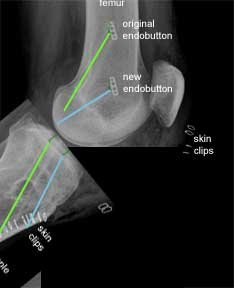

Revision from trans-tibial to 'more anatomic'

This is an X-ray of a patient who had a trans-tibial ACL reconstruction performed in another hospital. This was revised to a ‘more anatomic’ single bundle ACL, when it failed. The old femoral tunnel is highlighted in green and the new femoral tunnel is highlighted in blue.

This X-ray is from the front as before. The original endobutton was not removed. If you follow the line of the new femoral tunnel it is clear that it has been drilled from an antero- medial portal as the blue line points to two skin clips at this point.

There are further skin clips indicating an antero-lateral arthroscopic portal and a medial proximal tibial incision made to harvest the hamstring graft and drill the tibial tunnel. The larger white implant at the lower end of the tibia is a staple. This is put in for extra support in revision cases. This is in addition to the PEEK screw which was described earlier.